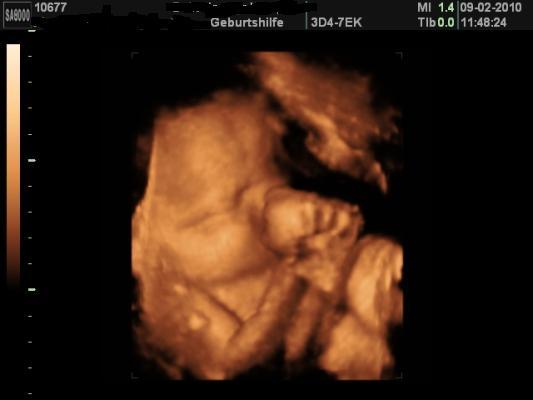

Hallo Mädels, komme gerade von der VU. Mit Aaliyah ist alles in Ordnung, sie wächst und gedeiht, sei aber trotzdem recht zierlich. Hier ein paar Daten (vom Baby gibts keine mehr): SSW 34+6 SL Gewicht: +13,2kg Blutdruck: 120/60 Blut und Urin o.B. Hb-Wert: 11,8 CTG war auch i. O. Hier noch ein aktuelles Bildchen von unserer Kleinen, ich bin soooo verliebt vlg Manu

Bild zu VU Bericht mit 3D Foto - Forum für März - Mamis